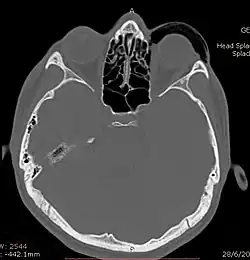

Computed tomography (CT)

CT scan taken from the transverse plane demonstrating orbital emphysema.[39]

CT scan taken from the coronal plane demonstrating orbital emphysema.[39]

Computed tomography is effective and sensitive in the diagnosis of orbital emphysema,[3][37] as it can confirm the anatomical location and size of air, bony defects, indentation of the eyeball, and the condition of the optic nerve, as well as the presence of any extraocular muscle entrapment and herniation of preorbital fat into the sinus cavities.[3][15][38] The location of the orbital emphysema is present near the site of the fracture.[1][3] The scans are usually taken along the transverse plane. Transverse images allow the evaluation of fractures in medial and lateral orbital walls. By reformatting these transverse images or taking coronal images, the examination of orbital floor and roof is permitted. Helical scanning is preferred as it has a lower imaging time and radiation dose comparing to conventional scanning, especially when reforming transverse helical scans into coronal images.[3] The staging of orbital emphysema can then be determined with visual acuity examination and ophthalmoscopy.[6] A disadvantage of using a CT scan is that when detecting air after orbital trauma, the presence of a wooden foreign object can give a false positive result of orbital emphysema. The wooden object can mimic the presence of orbital emphysema. Therefore, patients’ medical history is crucial in making the correct diagnosis.[3]